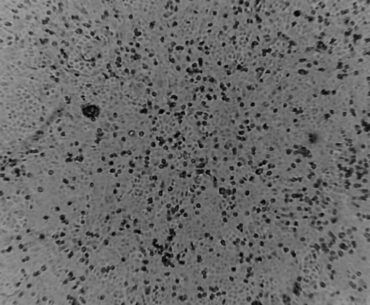

2019 novel coronavirus in culture

Peter Doherty Institute for Infection and Immunity (Doherty Institute) scientists have successfully grown the 2019 novel coronavirus (COVID-19) from a patient sample, providing laboratories around the world with crucial information to help combat the virus. Keep up to date with…